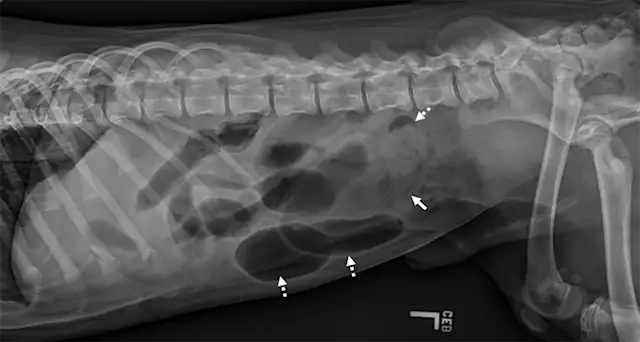

Left lateral image showing segmental dilated gas-filled intestines (dashed arrows) with heterogeneous soft tissue in a small intestinal segment (solid arrow) in a dog. The foreign material was cloth, and the diagnosis was small intestinal mechanical obstruction. Exploratory laparotomy was performed.